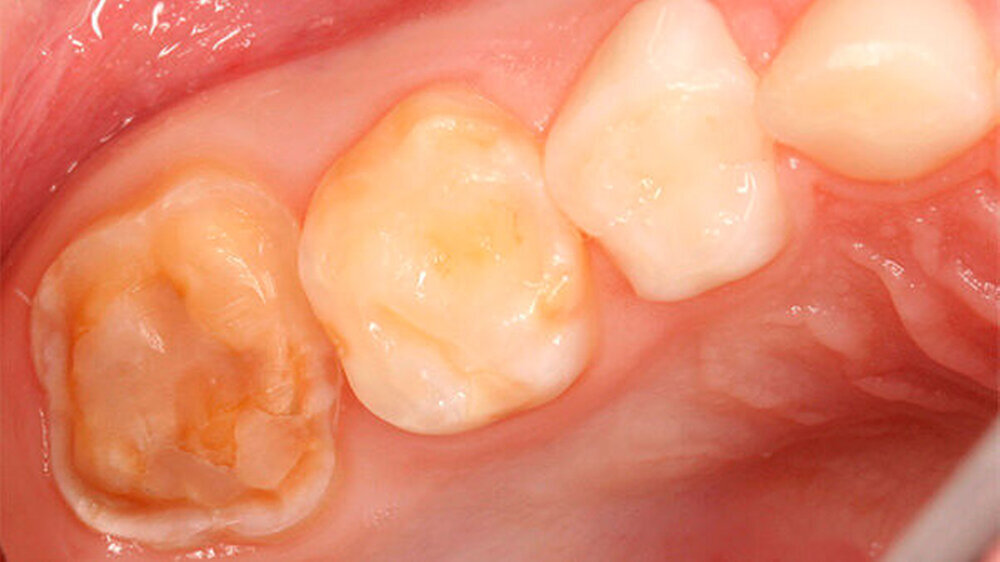

Zusätzlich zu den Frontzähnen waren die Molaren in sehr unterschiedlicher Ausprägung betroffen. Dies reichte von lediglich kleineren Opazitäten bis zu darüber hinausgehenden Schmelzverlusten: Im ersten Quadranten war Zahn 16 klinisch vollkommen unauffällig, hier zeigte aber der zweite Milchmolar insbesondere bukkal Opazitäten und Einbrüche des Schmelzes (Abbildungen 3 und 4) auf.

Zu ergänzen ist, dass die mesio-bukkale Opazität an Zahn 65 zwischen dem Zeitpunkt der Aufnahme der Patientin und der Präparation wenige Wochen später einen Einbruch der Schmelzoberfläche aufwies (Abbildungen 4 bis 6).